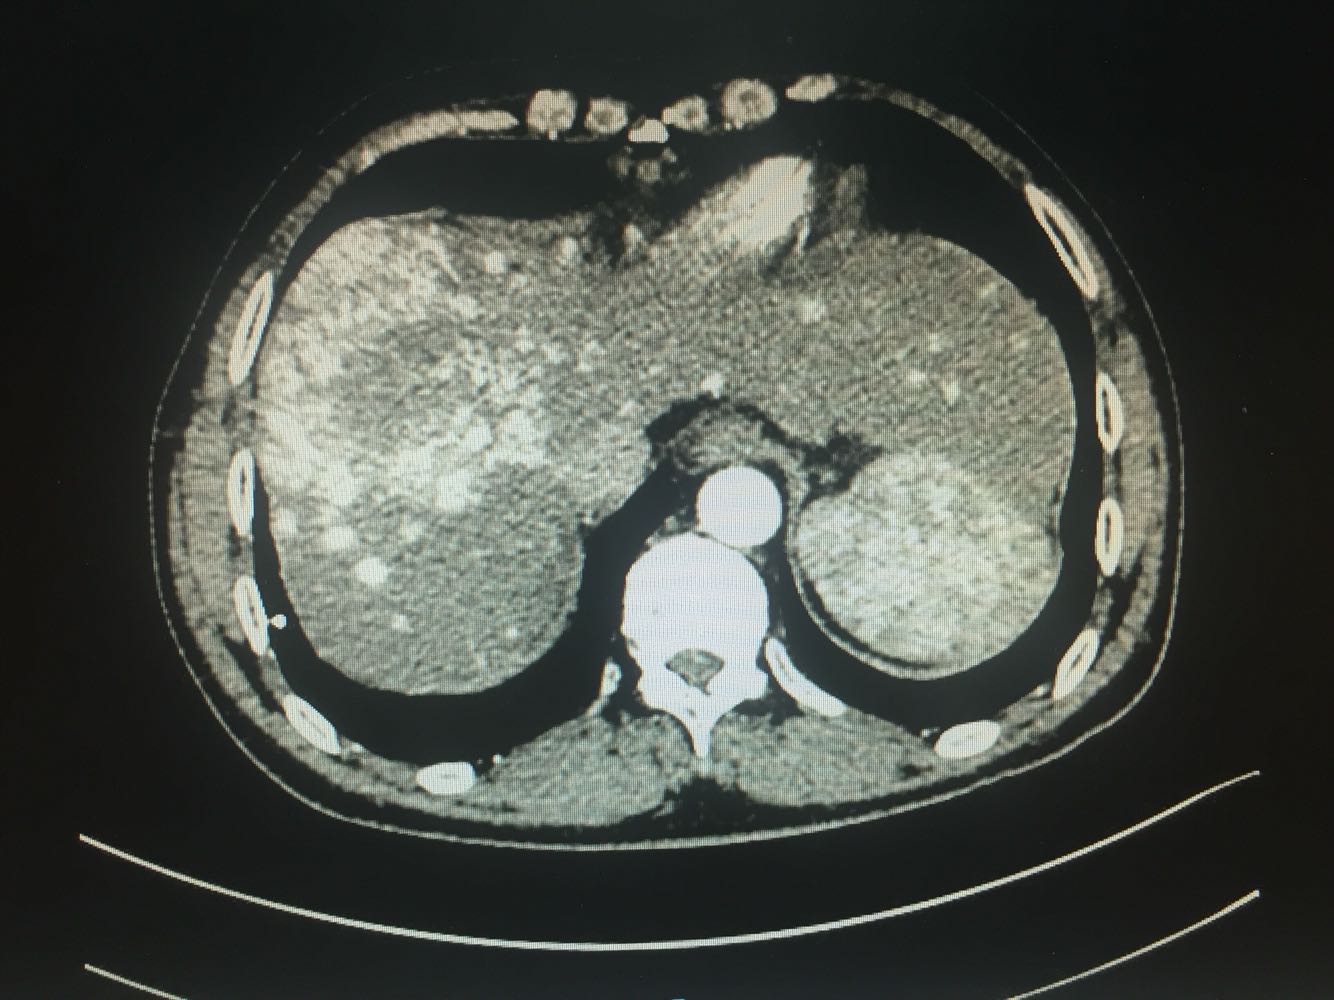

出院一月后复查,行增强CT扫描,肿瘤明显缩小,肝功能正常,乙肝病毒复制转阴,建议继续口服恩替卡韦抗病毒治疗

乙肝肝硬化,原发性肝癌,保肝抗病毒治疗,及TACE